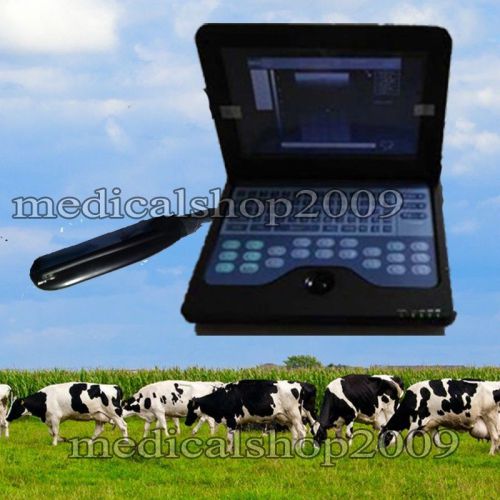

Veterinary Laptop B-Ultrasound Diagnostic System scanner 3.5mhz covex probe P2

Hot!! CMS600P2 VET veterinary Laptop Ultrasound Scanner System 6.5M Rectal Probe